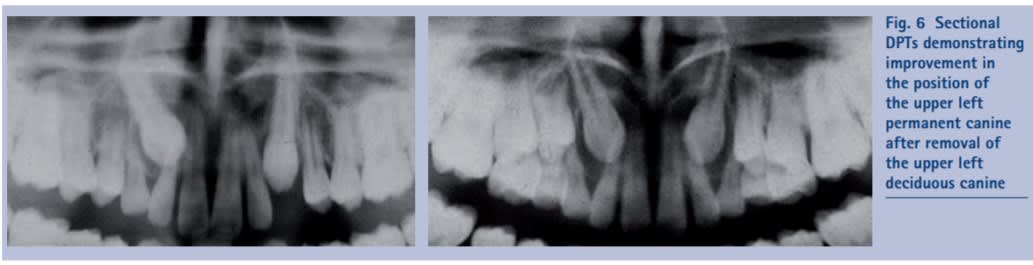

Je t'offre celui des Anglais:

https://www.nature.com/articles/sj.bdj.2012.726.pdf

Ils disent que c'est parfois intéressant, ils insistent sur l'intérêt de maintenir l'espace. Je te colle leur image, elle est sympa, est quasi similaire à la tienne!

La cochrane dit par contre qu'aucun essai clinique n'est convaincant, on a juste des études de pas super qualité.

L'un dans l'autre, çà ne me parait ni aberrant, ni menant à un succès garanti.